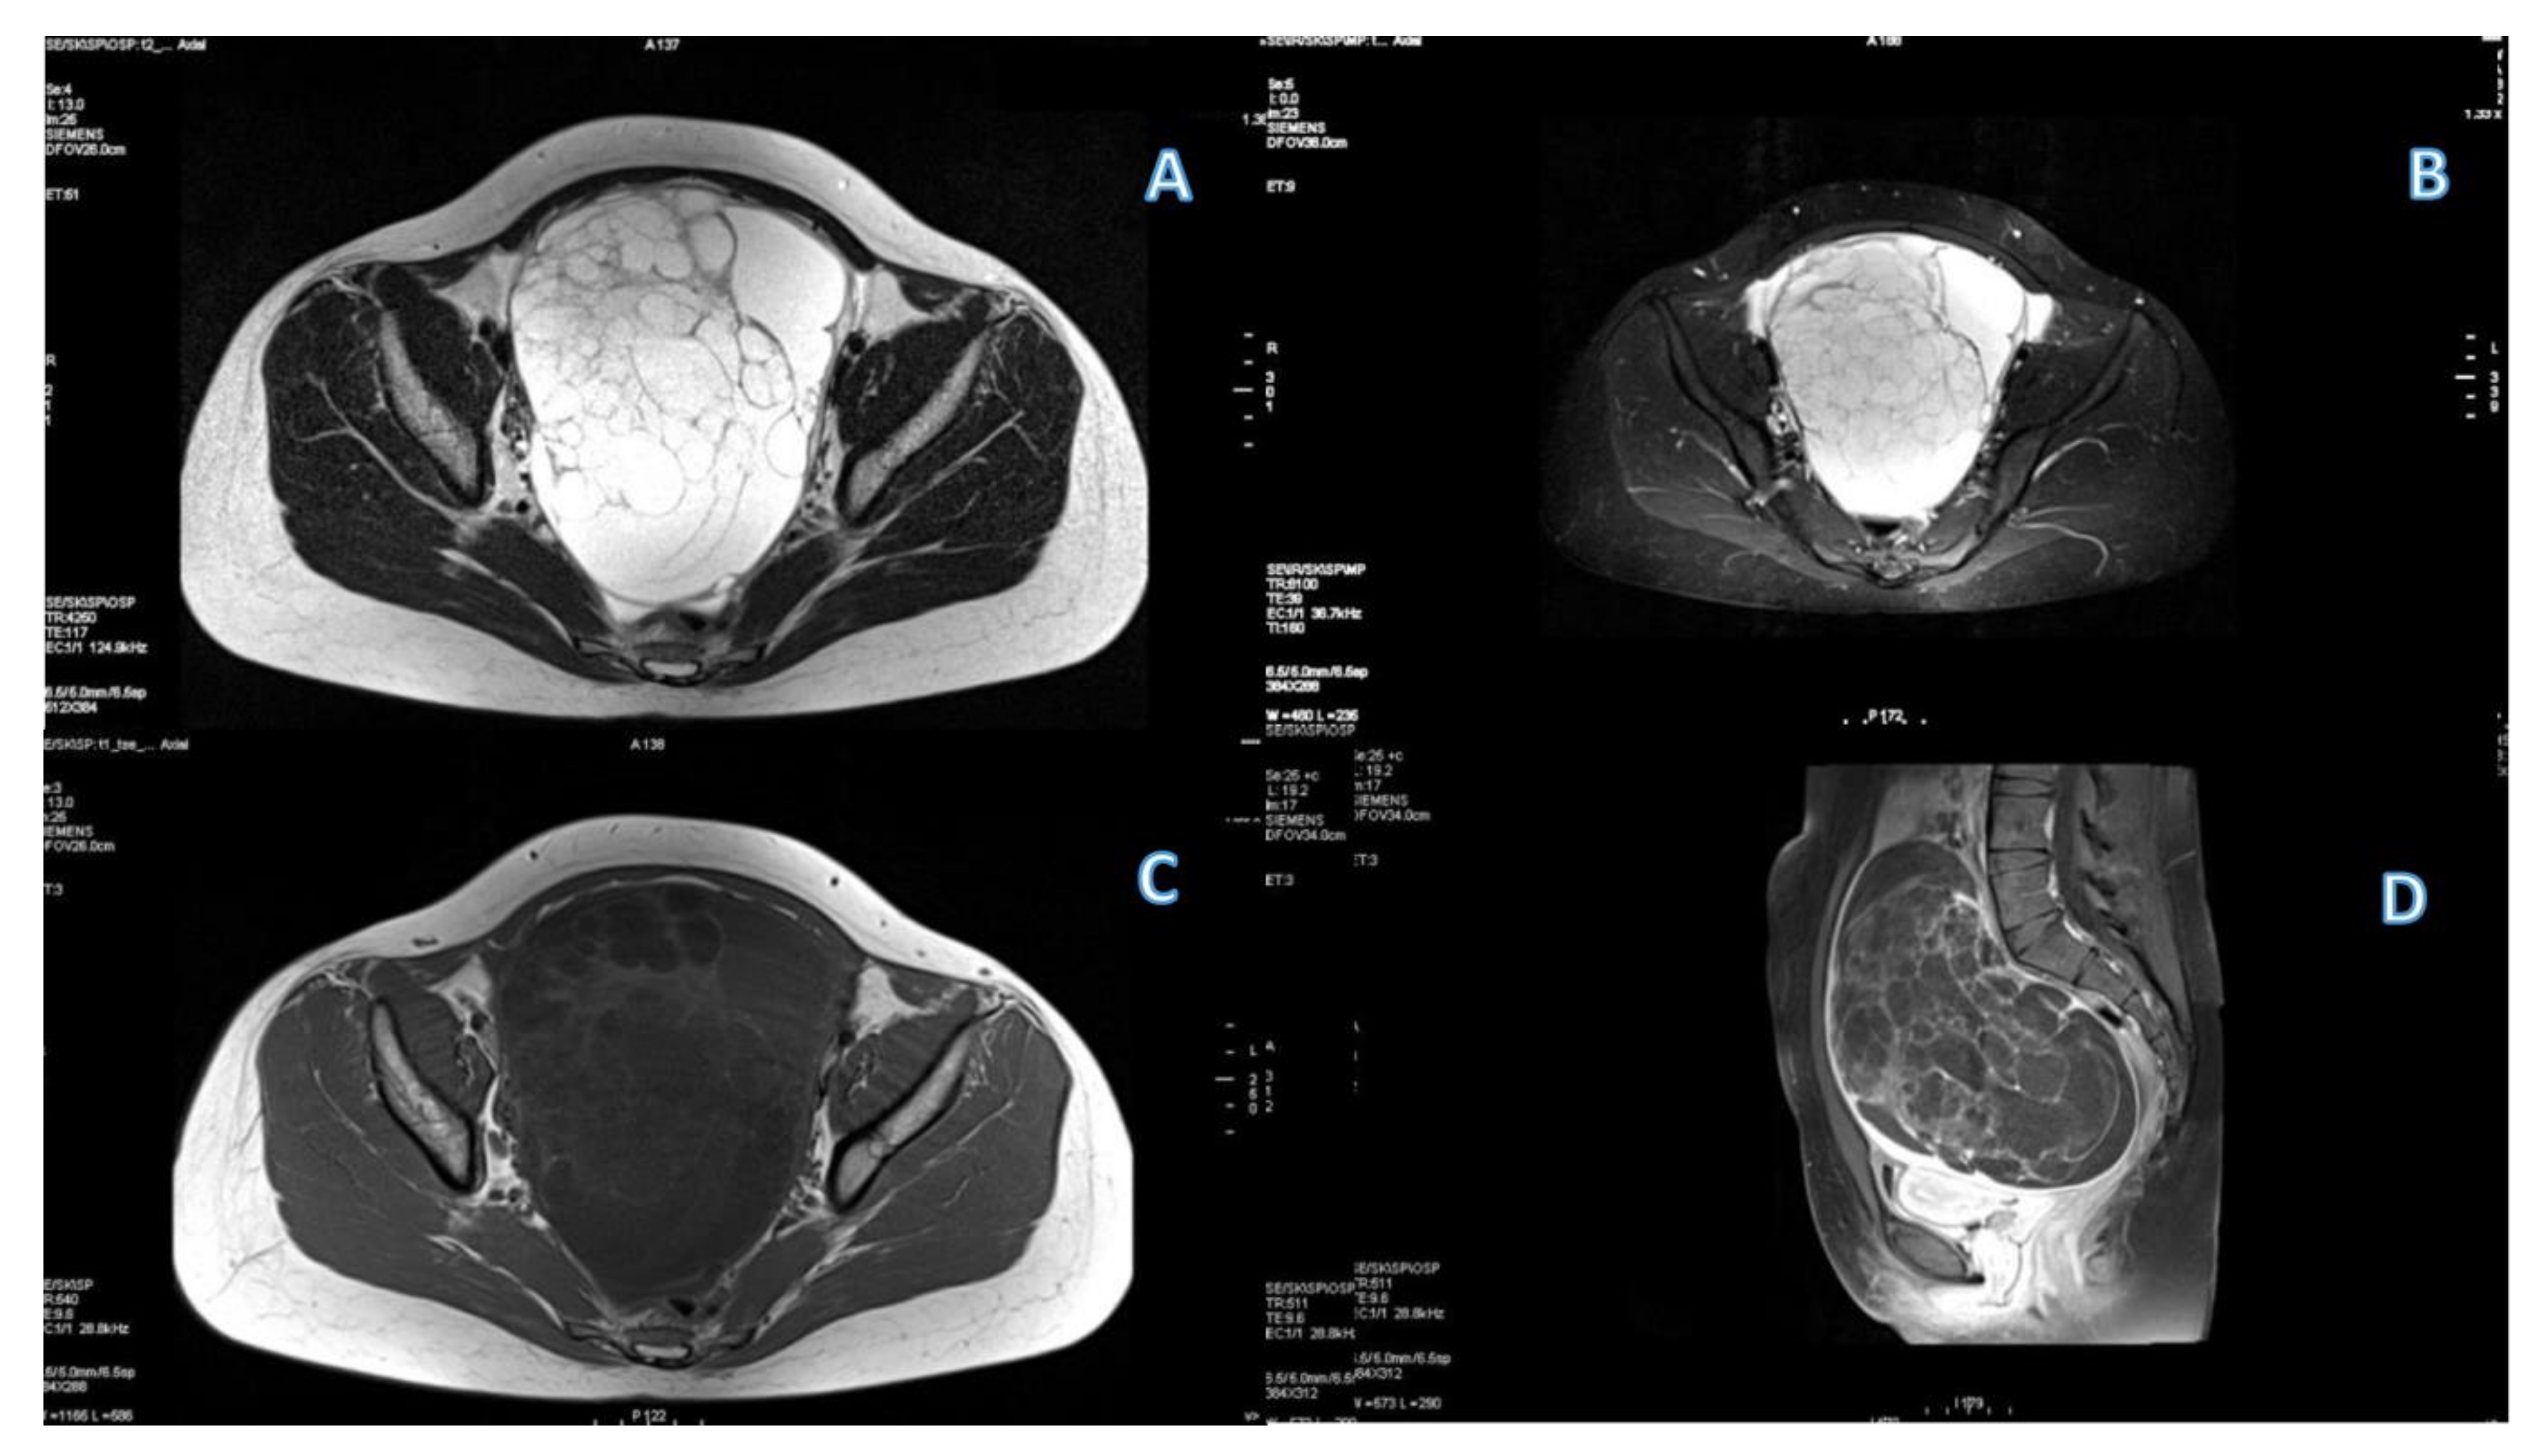

3.1. Primary Tumor DWI

3.4. ROC Curve for LGSC vs. MOC